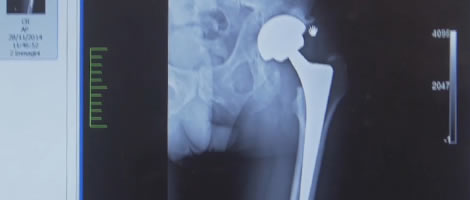

Da oltre 15 anni eseguo interventi di protesi d’anca e ginocchio con diverse tecniche.